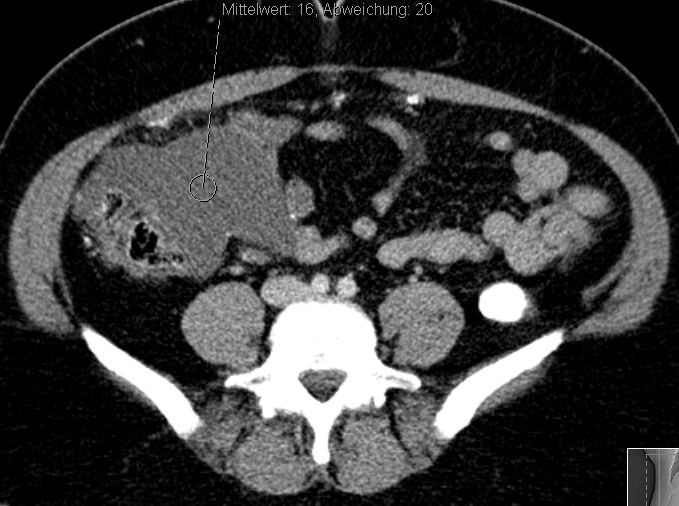

6 Monate später Lebermetastasen.![]() |